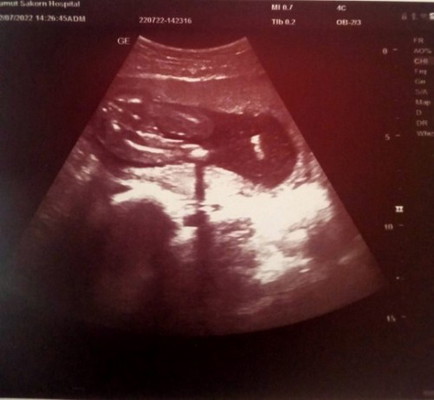

น้องผู้หญิงหรือผู้ชาย

น้องหนีบไม่ชัดเลยค่ะ